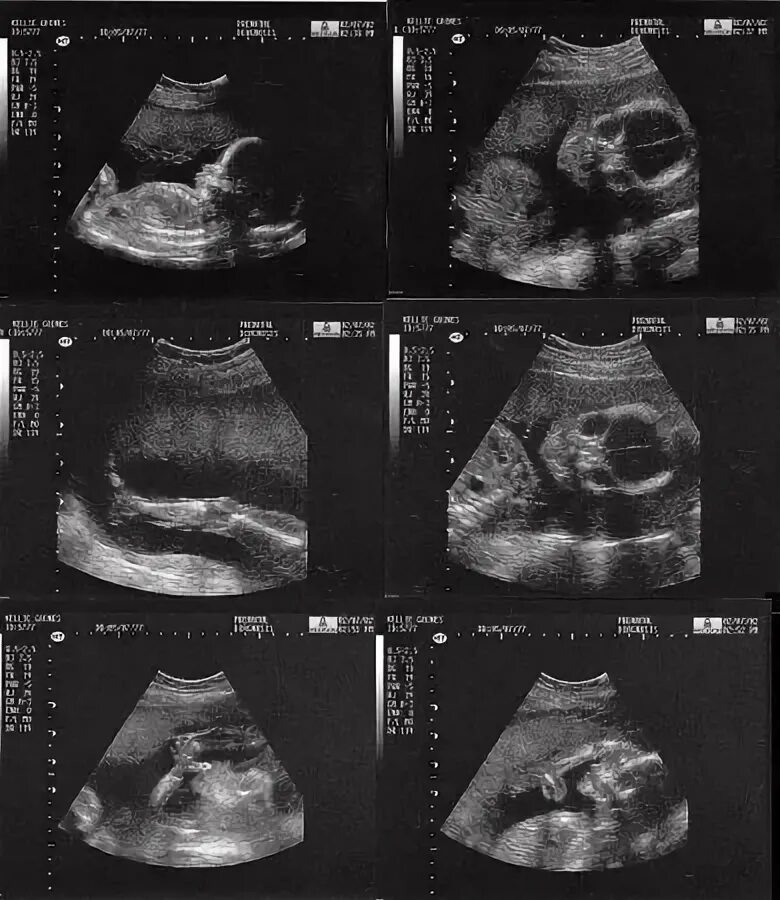

Узи 22 недели